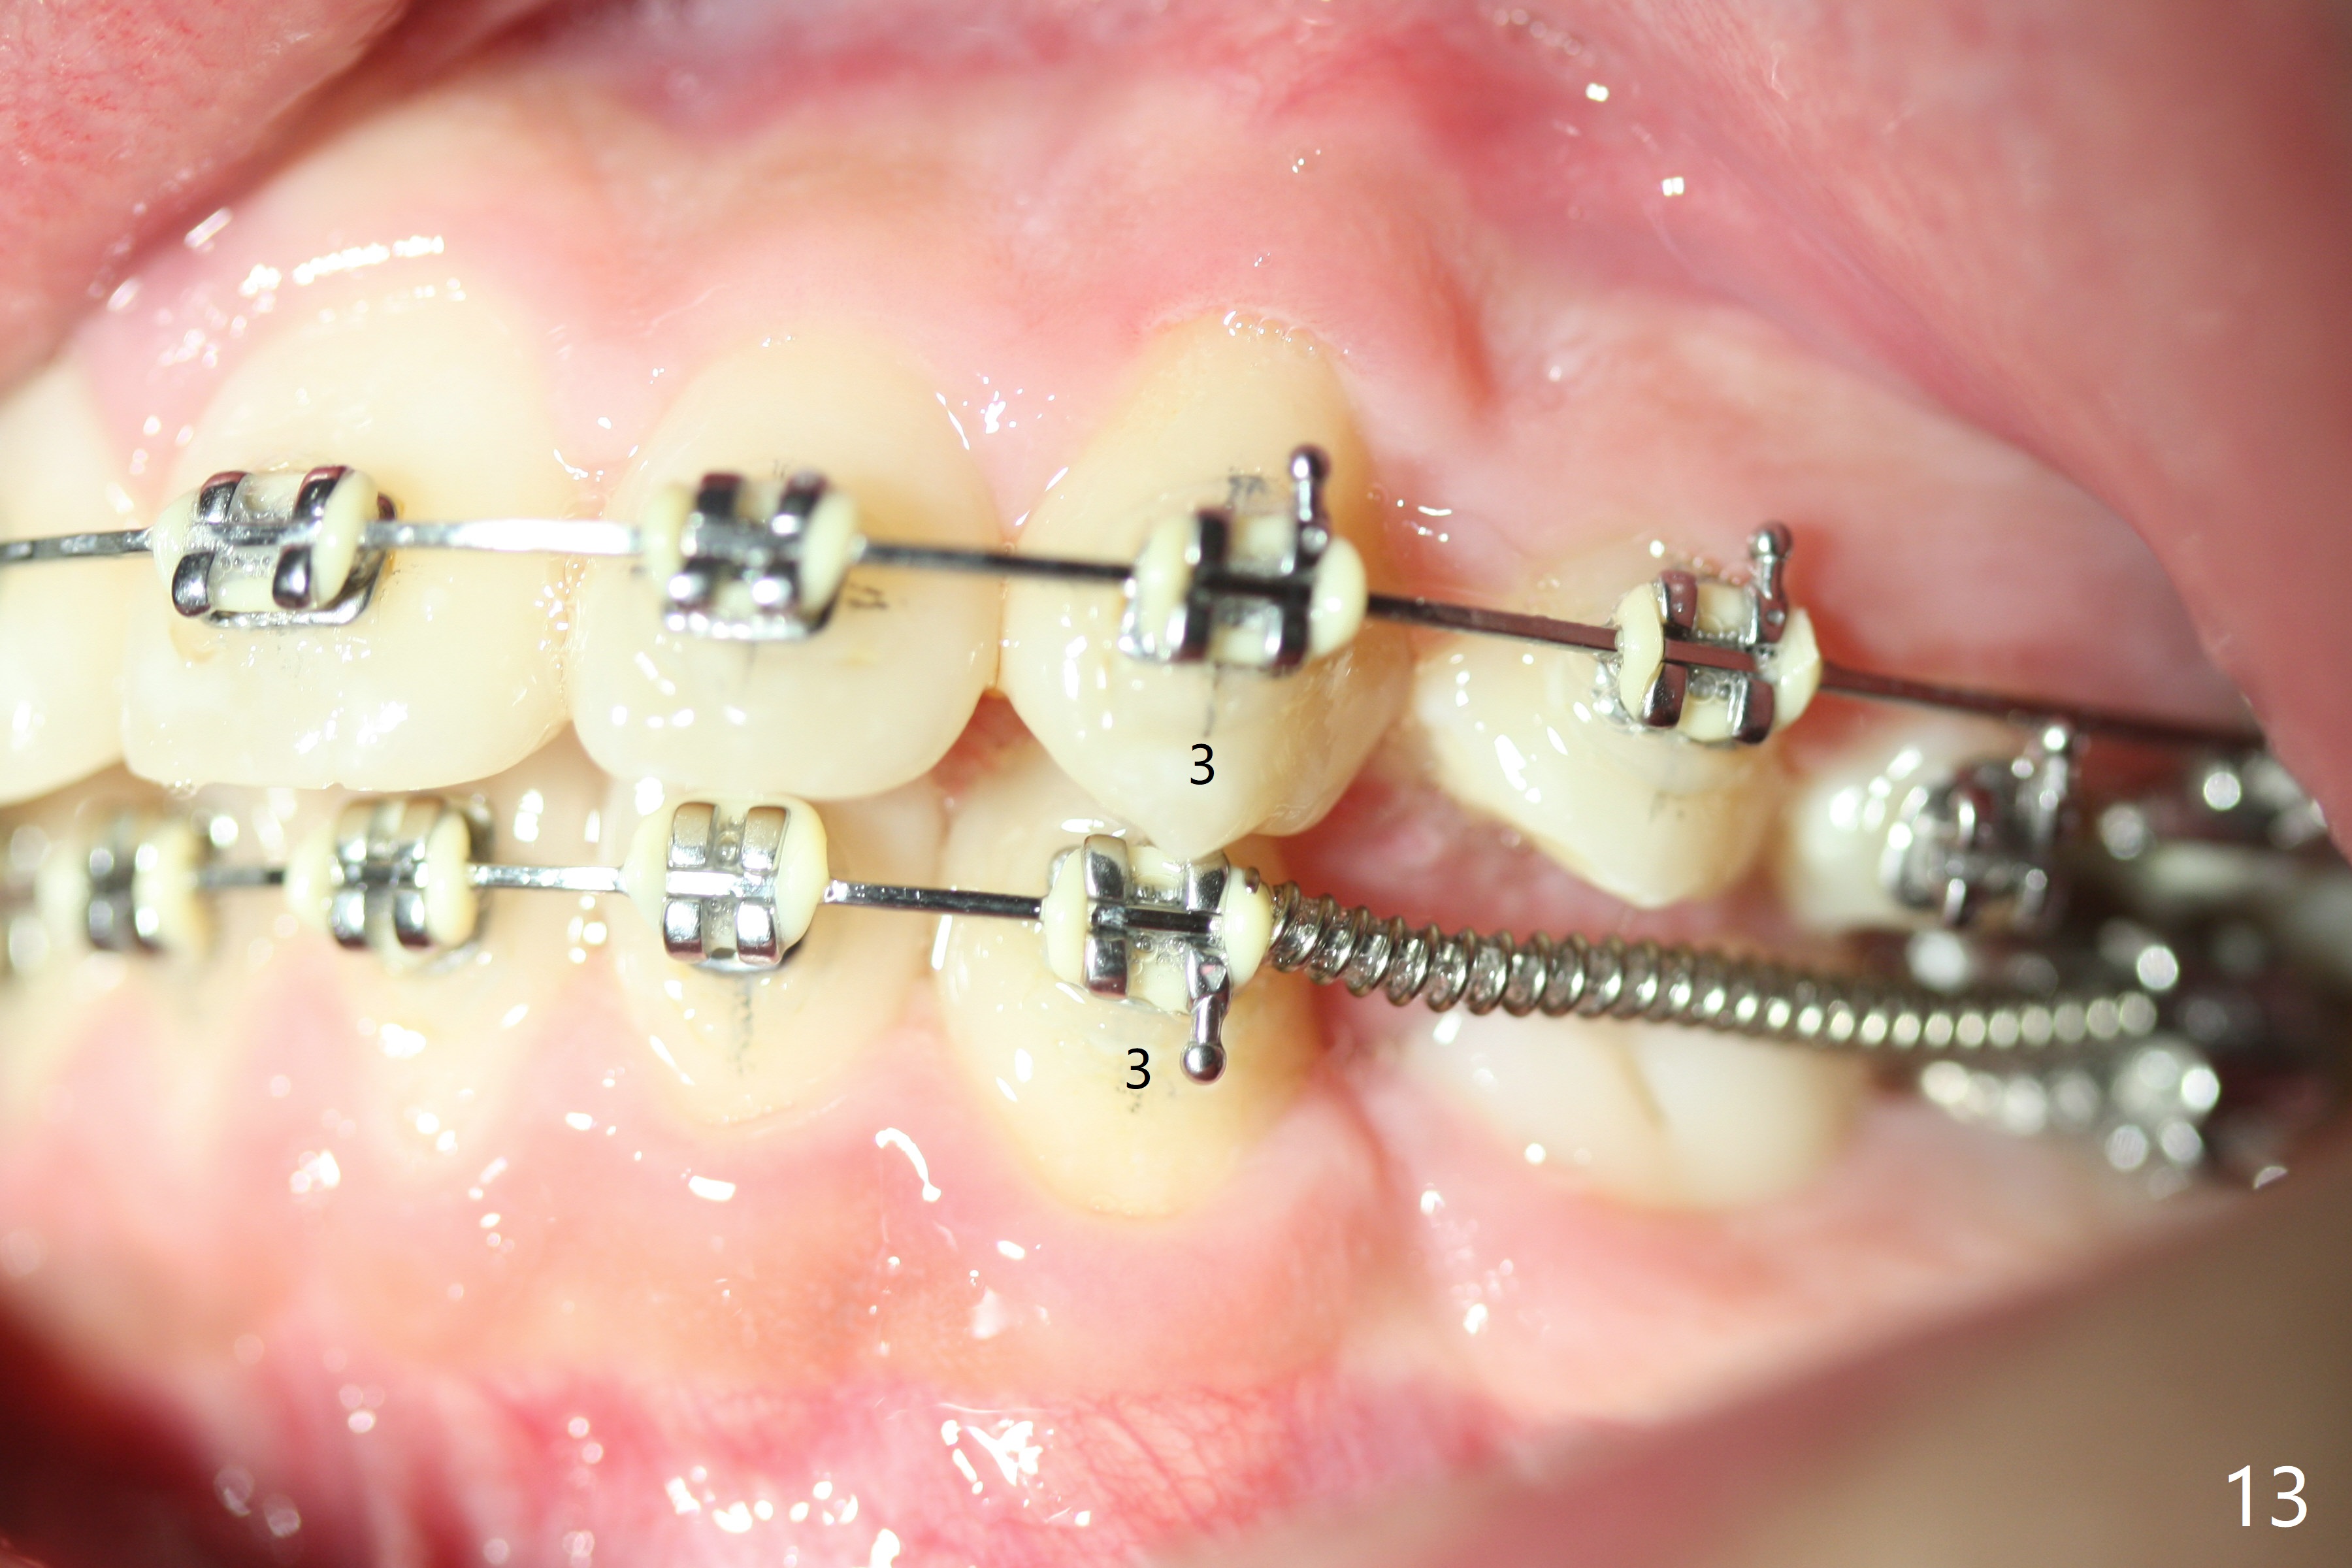

Eight months post banding, the interdigitation on the right side seems to be within normal limit (Fig.10), while the lower dental midline appears to be deviated to the left (Fig.11) with anterior overjet (Fig.12). The left canines remain Class II; open coil spring is placed between LL3-6 with intention to reduce anterior overjet and correct the lower midline deviation (Fig.13). Four weeks later, LL3 does not seem to be mesialized. It appears that the long open coil spring between LL3-6 is not effective. A molar band is added to LL E (Fig. 14,15). When a molar band is placed in LL7, an upper niti wire will be placed in the lower arch to expand the arch. When arch wire turns into thicker one, place open coil spring between LL3 and E.